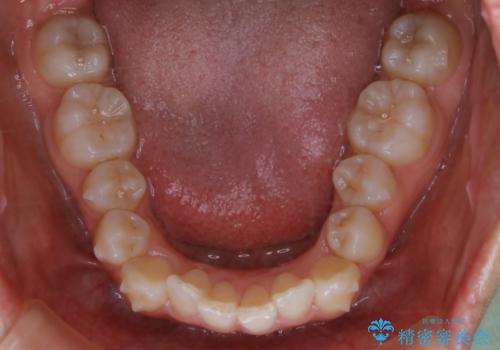

- 上の前歯が大きい事と下の前歯のがたつきを気にされてご相談にいらした方です。上の2番目の歯が矮小歯であったため、矯正治療にて歯のスペースを作った後、矮小歯には被せ物をして前歯のバランスを整えました。

歯科技工士さんとの打ち合わせを重ね、周囲の歯としっかりなじむ天然歯のような被せ物をお作りすることが出来ました。

矯正治療と補綴治療をうまく組み合わせることで、美しい口元に仕上げることが出来ました。矯正治療、補綴治療をまとめて行える総合歯科治療を体現した治療といえます。